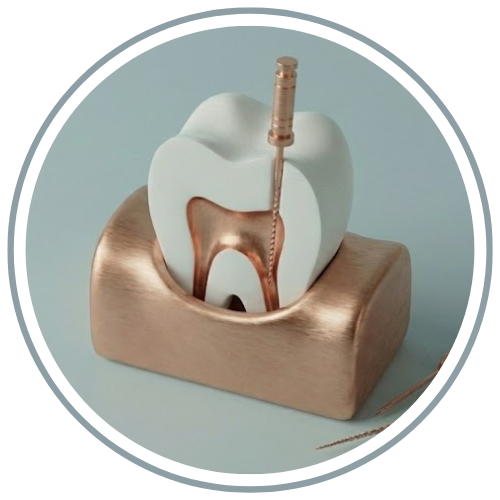

جرمگیری دندان چیست؟

بزاق دهان به طور طبیعی حاوی املاح کلسیمی است که با گذر زمان روی دندانها و نواحی نزدیک لثه رسوب میکنند. این رسوبات که با مسواک زدن معمولی پاک نمیشوند، "تارتار" یا "جرم" نام دارند. جرمگیری (Scaling) فرآیندی است که طی آن، دندانپزشک با ابزارهای خاص، این لایههای سخت را از روی دندان و زیر لثه برمیدارد. برخلاف باور غلط، جرمگیری دندان را نازک نمیکند، بلکه جرمی که دور دندان را گرفته حذف میکند.

۱. معاینه اولیه: بررسی وضعیت لثهها و میزان جرم.

۲. جرمگیری اولتراسونیک: استفاده از قلمهای لرزشی با آبپاشی برای خرد کردن و شستن جرمها.

۳. جرمگیری دستی (در صورت نیاز): برای نواحی حساس زیر لثه و بین دندانها.